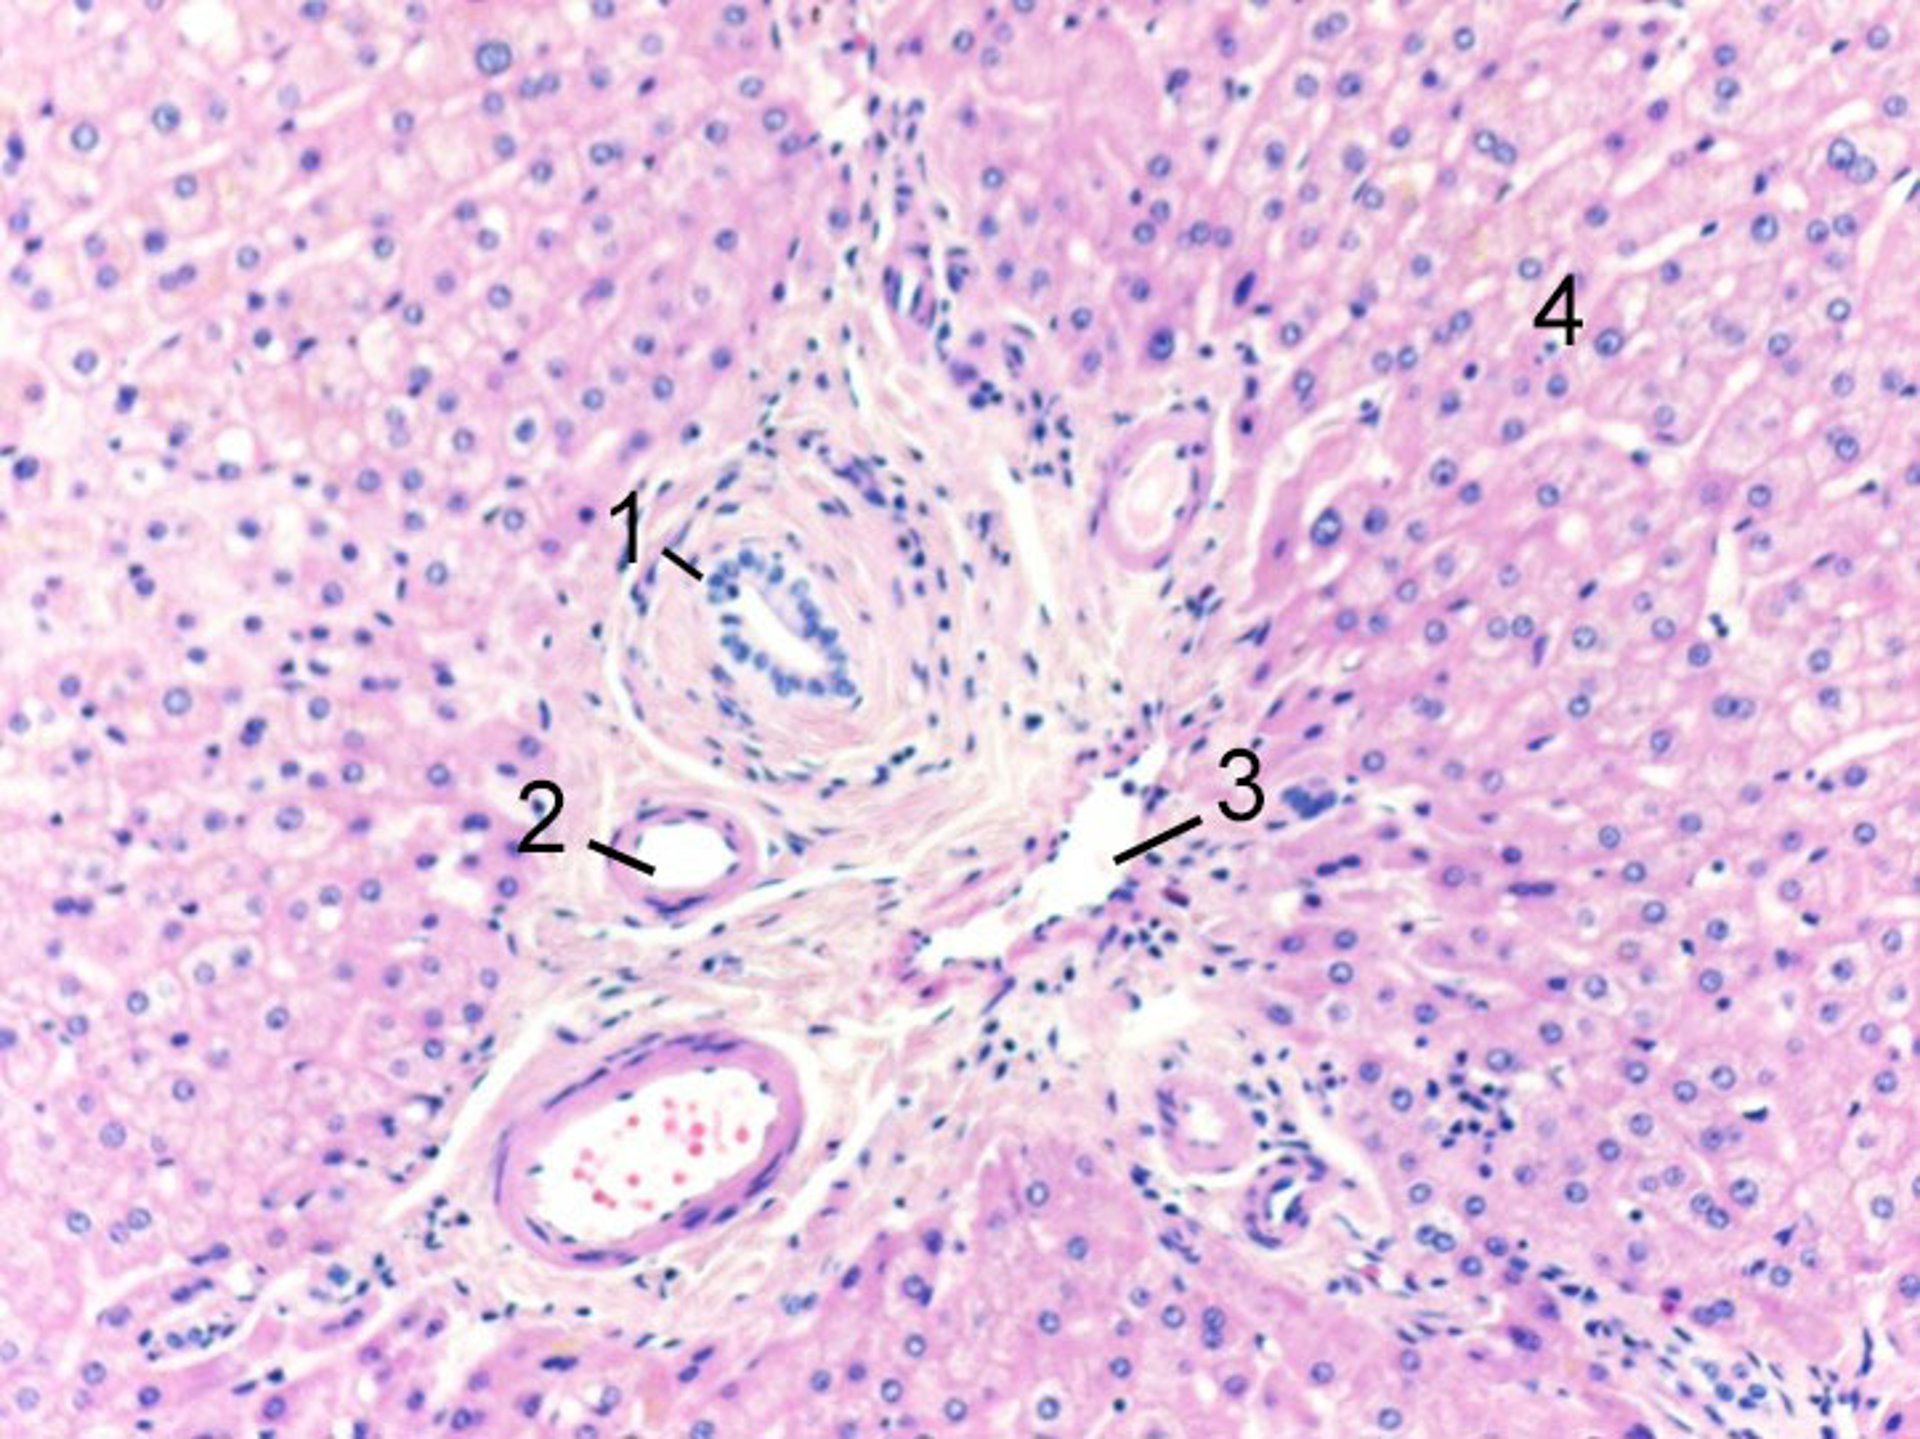

Au niveau cellulaire, les hépatocytes sont organisés au sein d'un lobule, qui est constitué de groupes de cellules de forme hexagonale avec une veine hépatique au centre, et des triades portes autour de la périphérie. Les espaces portes se composent de branches terminales adjacentes et parallèles des voies biliaires, des veines portes et des artères hépatiques. Le sang circule depuis l'artère hépatique et la veine porte (dans les triades portales) en périphérie, à travers les sinusoïdes entre les hépatocytes, vers la veine centrale. Par conséquent, les hépatocytes au centre du lobule sont les plus sensibles à l'ischémie car l'oxygène et les nutriments ont été extraits par les hépatocytes lors de l'écoulement du sang à travers les sinusoïdes provenant de la périphérie. Des canaux plus petits, appelés canalicules biliaires, drainent la bile sécrétée par les hépatocytes dans les voies biliaires intrahépatiques en périphérie.

Image courtesy of Danielle Tholey, MD, and M. Isabel Fiel, MD, MS, FAASLD.